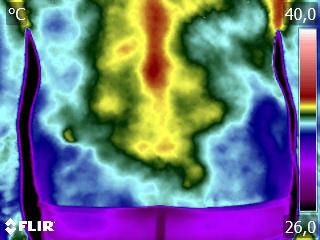

Respeitando todos os outros métodos, a Termografia Infravermelha coloca de forma clara, e em tempo real, as anomalias apresentadas. Assim, temos um método único capaz de gerar informações precisas e em tempo real para tomada de decisão.

Isso não se limita apenas a área tecnologia, mas inclusive das biociências. Pois permite a você, carto colega, a ter as informações necessários para fechar uma avaliação e ou monitorar o tratamento do seu paciente.

Dito isso, a termografia de longe é nosso maior aliado na clínica:

“Nenhum Método, tomado isoladamente, possui a capacidade da Termografia Infravermelha de permitir a avaliação, de forma rápida, segura e acessível, da condição da funcional do seu paciente, considerando as áreas clínicas da Fisioterapia e Terapia Ocupacional”.